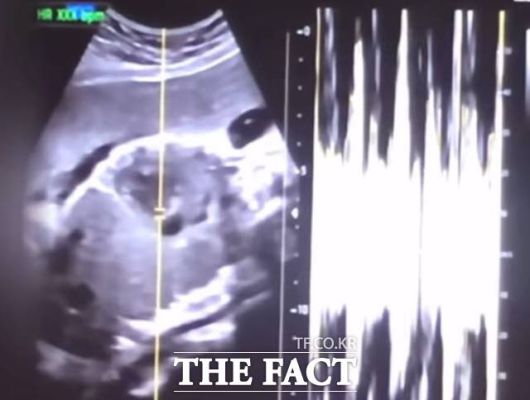

사진은 낙태한 산모의 유튜브 동영상에서 캡쳐한 초음파 사진과 심박 그래프./서울중앙지검 |

이 사건은 산모 권 씨가 자신의 유튜브에 36주차 낙태 경험을 공개하면서 알려졌다. 논란이 커지자 보건복지부는 지난해 7월 경찰에 수사해달라는 진정을 냈다.